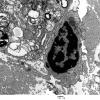

PERIPHERAL NEUROPATHY

4 AXONAL DEGENERATION

4 Macrophages